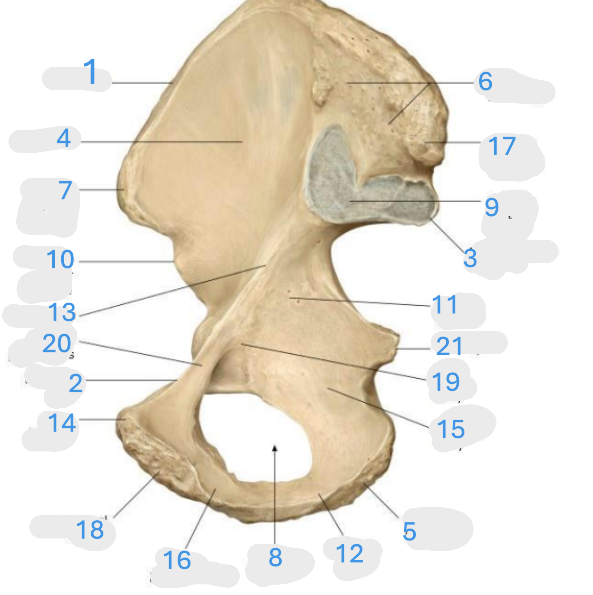

Where is the posterior inferior iliac spine

1

Where is the gluteal surface

2

Where is the iliac crest

3

Where is the posterior superior iliac spine

4

Where is the anterior gluteal line

5

Where is the anterior superior iliac spine

6

Where is the greater sciatic notch

7

Where is the inferior gluteal line

8

Where is the ischial spine

9

Where is the acetabular rim

10

Where is the lesser sciatic notch

11

Where is the obturator foramen

12

Where is the ischial tuberosity

13

Where is the anterior inferior iliac spine

14

Where is the acetabular notch

15

Where is the acetabulum

16

Where is the lunate surface

17

Where is the pubic tubercle

18

Where is the acetabular fossa

19